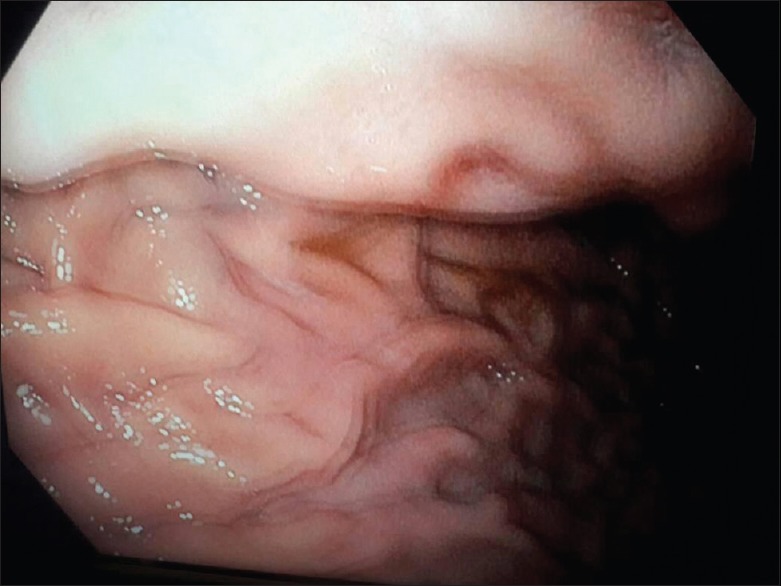

Ectopic Pancreas Causing Partial Gastric Outlet Obstruction: A Case Report and Review of Literature.

Ectopic pancreas is a rare cause of gastric outlet obstruction, perhaps rarer still among Africans. Although the entity is known, the diagnostic challenges are enormous, especially in the poor-resource environment. Gastric outlet obstruction resulting from ectopic pancreas in an adult is the first of its kind in our center; we, therefore, present this case to describe the challenges faced with diagnosis, treatment, and the lesson learned. Ectopic pancreas should be considered in the differential diagnosis of gastric outlet obstruction.